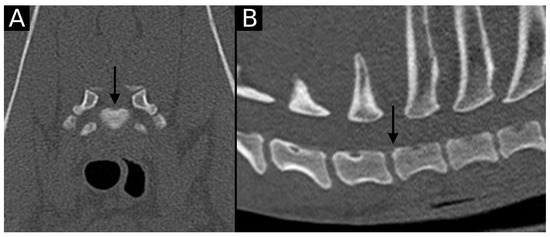

Figure 2. Transverse (A) and sagittal (B) reconstructions in bone algorithm. Mild contour irregularity and flattening lined by mild sclerosis are observed at the dorsal aspect of the T1 cranial endplate (arrow), consistent with EPJA Type A.